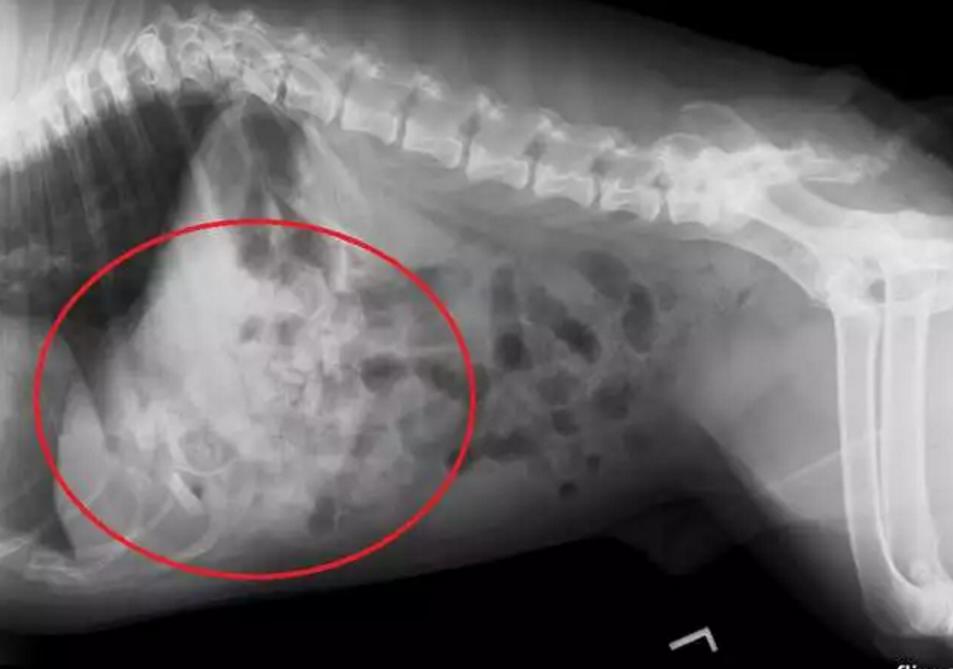

在狗狗的肚子里发现了21个安抚奶嘴。

在X光扫描后,医生发现狗狗胃里有大量的异物,因为情况紧急,兽医找来了助手,打算马上对狗狗进行手术,因为再等下去只会增加麻烦。

手术很成功,医生在英斗的肚子里取出了21个安抚奶嘴,而且有两个已经被狗狗的胃酸腐蚀得只剩下一半了,其余十几个看起来还很新。